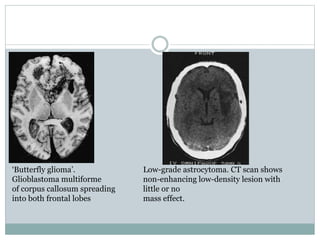

‘Butterfly glioma’.

Glioblastoma multiforme

of corpus callosum spreading

into both frontal lobes

Low-grade astrocytoma. CT scan shows

non-enhancing low-density lesion with

little or no

mass effect.